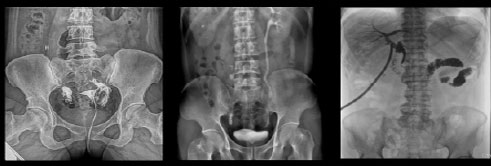

Рентгенологические исследования: рентгенография больших переломов костей и масштабное физическое рентгенографическое обследование, флюороскопия всех частей тела (грудная клетка, живот и т.д.), пищеводная ангиография, ангиография верхних отделов желудочно-кишечного тракта, полная ангиография желудочно-кишечного тракта, холангиография, Т-образная холангиография, ЭРХПГ, внутривенная пиелография, гистеросальпингография и т.д.